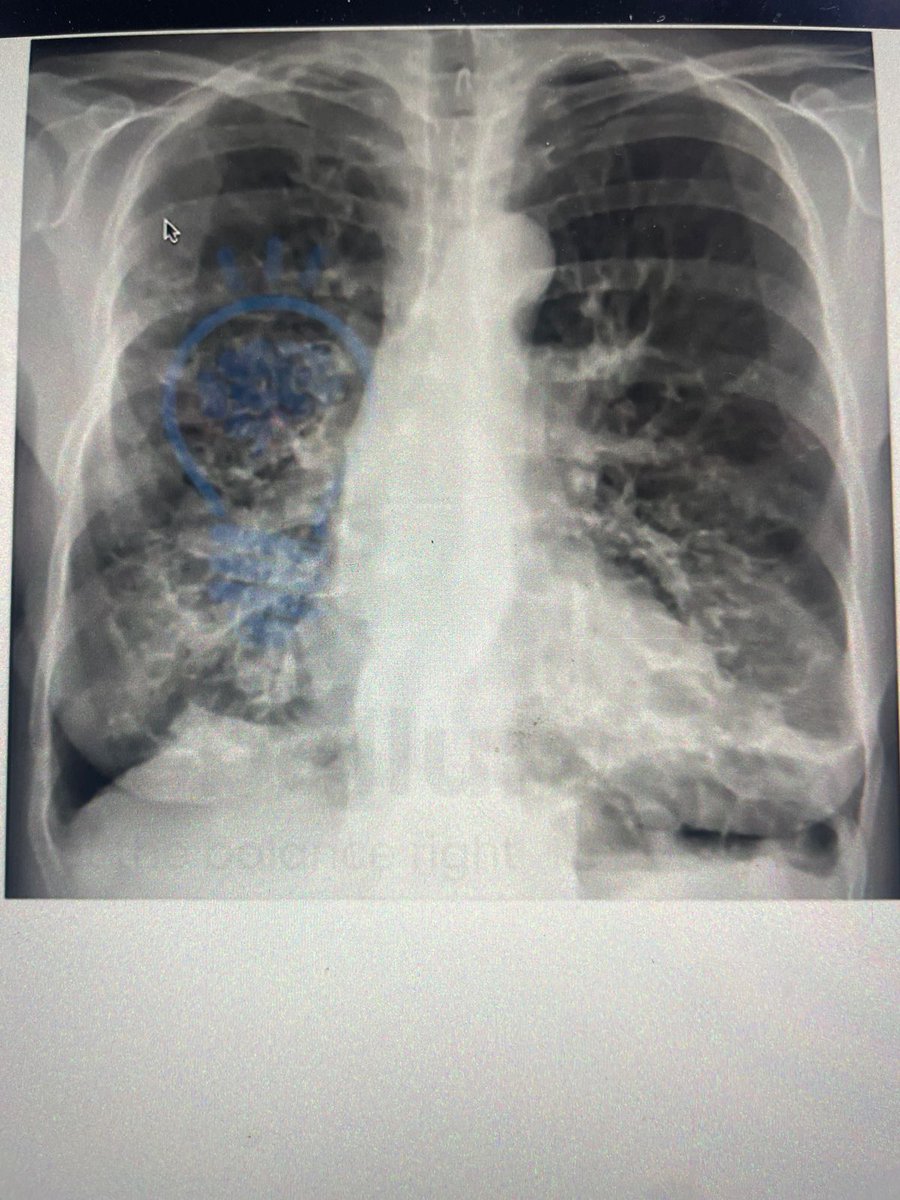

Can anyone help me visually differentiate between these two X-rays like I can see they are different but what's the terminology for them and also causative organism? #NEETpg #Inicet